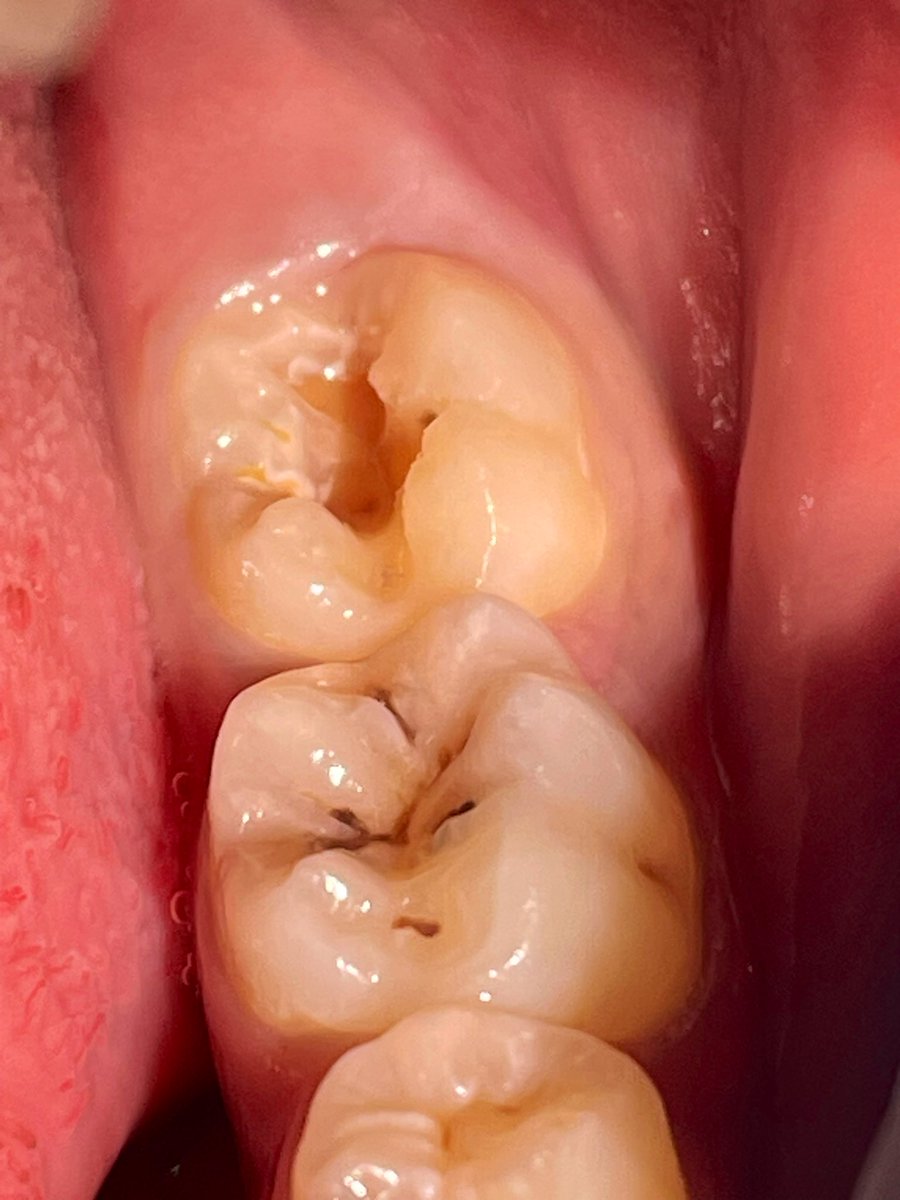

Intern Case Report – Endodontic Management of Tooth #22 with Periapical Abscess حضرت المريضة لاستكمال Endodontic treatment للسن رقم (22)، وكانت تعاني سريريًا من Periapical abscess مصحوب بأعراض ألم وتنميل. تم تحديد وتأكيد Working Length (WL) وبلغ 19.5 mm عند إجراء Canal negotiation تبيّن أن القناة Narrow canal، وعليه تم البدء بمرحلة Cleaning and Shaping باستخدام Hand files بشكل تدريجي حتى مقاس #35 بهدف إنشاء Glide Path آمن يسهّل إدخال الأدوات ويقلل من احتمالية حدوث Canal transportation أو Ledge formation أو Instrument separation. تم إجراء irrigation بصورة مستمرة خلال جميع مراحل التحضير لتعزيز Debridement وتقليل البكتيريا داخل القناة الجذرية. بعد تحقيق Preliminary enlargement مناسب، تم إدخال Rotary instrumentation ابتداءً من مقاس #20 لاستكمال Biomechanical preparation مع المحافظة على المسار التشريحي الأصلي للقناة. في نهاية الجلسة تم وضع Composite filling لضمان Coronal seal ومنع Reinfection .